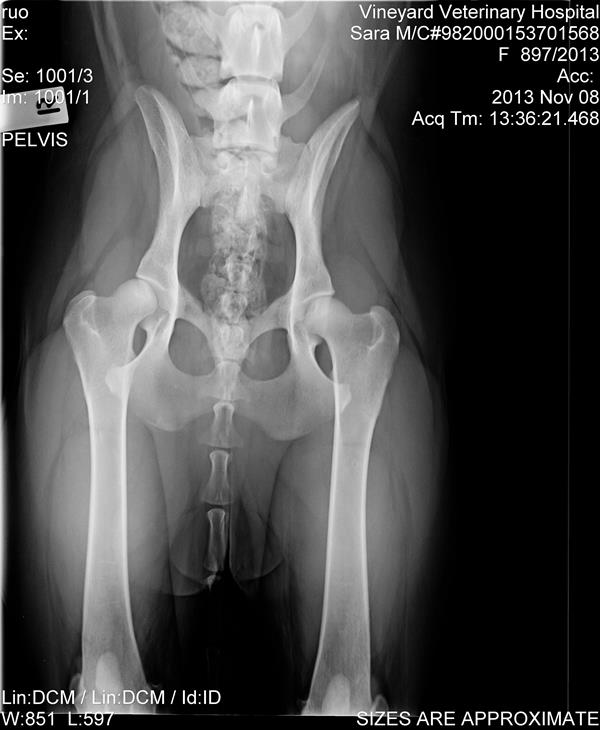

Ok I'm certainly not an expert but the hips look fairly good to me. The positioning is not perfect. As an example here is my now 2 year old male GSD. He needs another total hip replacement on the left side next year. But just for comparison for you. I would email the xrays you have to a couple of specialists for their opinion.

I had some feedback from someone i emailed with the scans, they look pretty good, was the comment.

"Her hips and elbows are fairly good. The hips - the right hip is just slightly shallow and just slightly loose - nothing to worry about, the left hip has a very slight thickening of the cranial acetabular edge, again nothing to worry about, her elbows are normal. There is a calcinosis ( calcium deposit next to one elbow - again not an issue, won't cause any lameness etc.

Her hips would probably score around 6-8 on the right and 4-5 on the left. The pass mark for the "A" stamp is a maximum of 8 points in total with no more than 3 points in any one area. Certainly would not be concerned about either of her hips or elbows as a long term issue,"